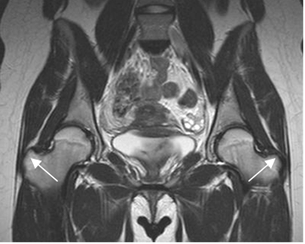

Los tendones de todos los grupos musculares, se aprecian como estructuras hipointensas en todas las secuencias, en relación con los sitios de origen e inserción. (Fig 21, 22 y 23).

Fig 21. Músculos normales.

A: RM coronal en T1 y B: RM coronal en STIR. Origen de músculos isquiotibiales, hipointensos en todas las secuencias.